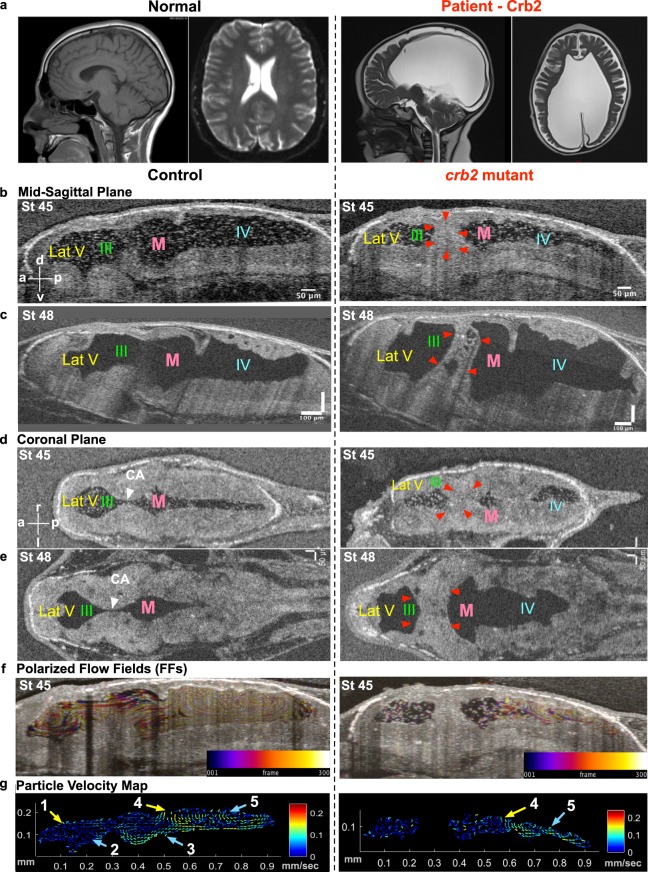

Figure 5. Hydrocephaly phenotype with CRB2 mutations. (a) CT scan of a normal brain and patient brain, with enlargement of the brain ventricles. (b) Mid-sagittal view (d) Coronal view using OCT shows reduction in ventricular size along with CA stenosis in crb2 F0 CRISPR mutant tadpole brain at stage 45 as compared to controls. (c) Mid-sagittal view (e) Coronal view of control and crb2 F0 CRISPR mutant tadpole raised to stage 48 shows enlargement of the ventricles as compared to controls. This result was seen in 3 animals that survived to this later stage. (White arrow head â CA, red arrowheads â stenosis of CA). (f) Stage 45 tadpole particle tracking shows the impairment of the flow fields in the lateral 3rd and midbrain ventricles, but normal flow in the fourth ventricle for the crb2 F0 CRISPR mutant as compared to the control. (g) 2D Particle Velocity Map shows loss of FFs 1-3 and intact FFs 4-5. (Lat-V: lateral ventricle, III: 3rd ventricle, M: Midbrain ventricle, IV: 4th ventricle). |